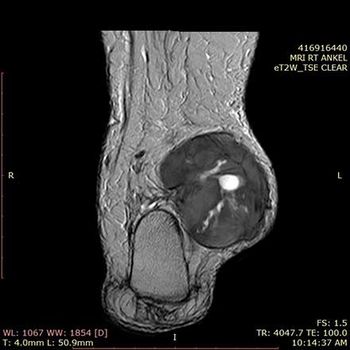

Case History: A 62-year-old patient with a history of swelling on medial aspect of ankle for six months.